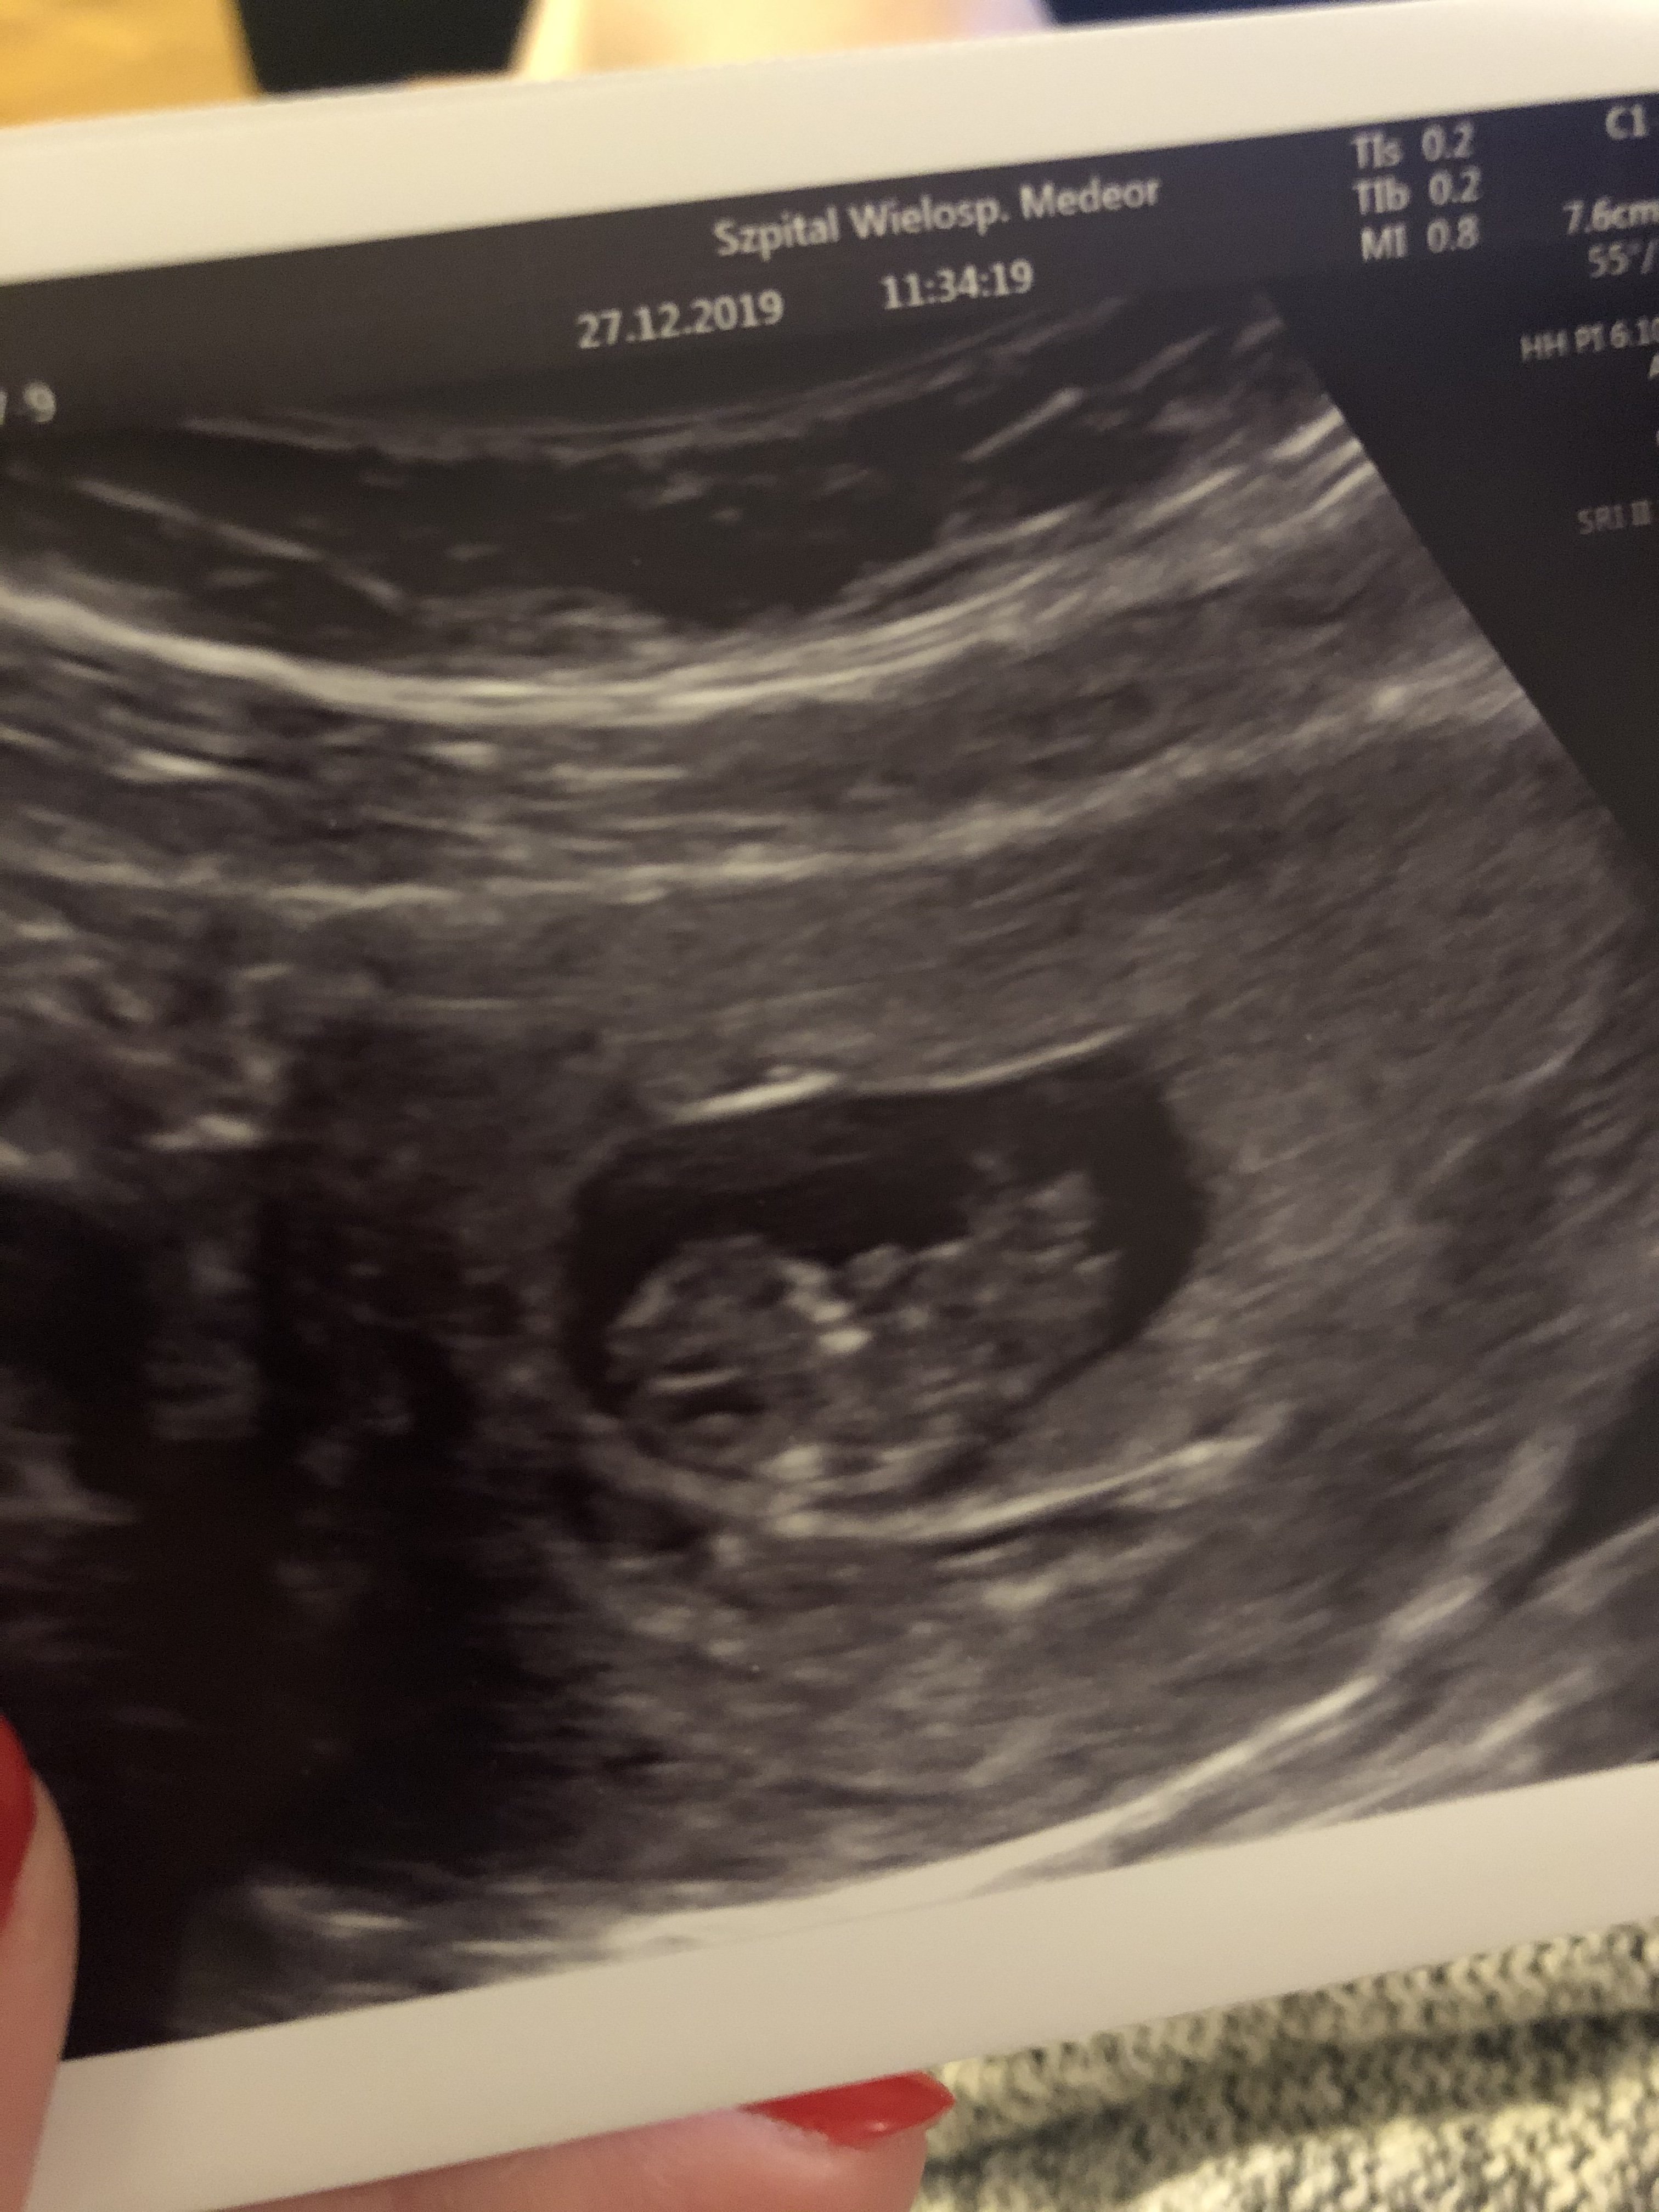

Hej hej ! Jak lekarz mowil ze to jeszcze mlodsza ciaza nic 5tc to chyba bardzo prawdopodobne ze mogl nie widziec jeszcze zarodka. Trzymam kciuki ! Nie martw się na zapasCześć Dziewczyny! Jestem tu nowa, dopiero się zarejestrowałam. 5 grudnia zrobiłam test, upragnione dwie kreski, chociaż jedna słabsza (był to dzień przed @), kolejne były już grube i mocnew 32 dc beta ponad 700, progesteron 42. Był to cykl stymulowany, owulacja 16-17dc. W 5 tyg +6 dni byłam na pierwszej wizycie. Niestety bardzo się zmartwilam... Chociaż lekarz twierdzi, że jest ok, tylko ciąża młodsza. Wg niego jest to początek 5 tygodnia. Pęcherzyk w macicy kształtu owalnego (lekarz nic na to nie powiedział) a w środku pęcherzyk zoltkowy, bez zarodka. Wstawiam zdjęcie z USG. Kolejna wizytę mam za tydzień. Objawy mdłości, bolacych piersi, zawroty głowy, senność. To moja pierwsza ciąża. Co o tym myślicie?

Na spokojnie. U mnie na tym etapie był tylko pęcherzyk 6mm tydzień później było już serduszko. Dużo zależy od sprzętu na gorszym usg w lux med w 6+2 lekarz dojrzał pusty pecherzyk nastepnego dnia usg u innego lekarza i na innym sprzęcie i pokazał się zarodek z bijącym sercemTwierdził że to początek 5 tygodnia. Czytałam, że pęcherzyk zoltkowy pojawia się w 5 tyg +2 do 5 tyg +5. No niby tak, ale miałam cykl stymulowany i wiem kiedy była owulka... Więc skąd to przesunięcie? Lekarz mówił, że zagnieżdżenie mogło być później...

Super! Który tydzień? W ogóle fajnie jakbyśmy pisały tydzień i dzień wrzucając zdjęcieMelduję się z dzisiejszym USG![]()

Dokładnie 9. Z CRL 9+1.Super! Który tydzień? W ogóle fajnie jakbyśmy pisały tydzień i dzień wrzucając zdjęciewtedy sobie patrzę i myślę: oho, tak będzie u mnie za tydzień